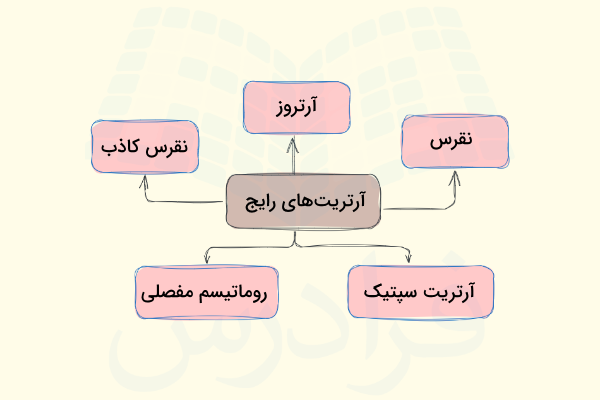

«آرتریت» (arthritis) یا التهاب مفصل انواع زیادی دارد، اما در این بخش به بررسی تمام آنها که بیش از ۱۰۰ نوع هستند نمیپردازیم و فقط تعدادی از رایجترین آنها را معرفی میکنیم.

- آرتروز یا «استئوآرتریت» (Osteoarthritis): رایجترین نوع آرتریت است که در طی آن غضروف موجود در زانو به دلیل استفاده بیش از حد یا افزایش سن آسیب میبیند.

- «روماتیسم مفصلی» (Rheumatoid arthritis): آرتریت روماتوئید یا روماتیسم مفصلی بیماری مزمنی است که میتواند اکثر مفصلهای بدن، از جمله مفصل زانو را تحت تاثیر قرار دهد.

- «نقرس» (Gout): نقرس نوعی التهاب است که در افرادی که رژیم غذایی پرپروتئینی دارند، شایعتر است. در حقیقت اختلال در متابولیسم پروتئین دلیل به وجود آمدن نقرس است و به طور معمول انگشت شست پا را درگیر میکند اما ممکن است زانو نیز درگیر نقرس شود.

- «نقرس کاذب» (Pseudogout): این بیماری ناشی از تشکیل کریستالهای حاوی کلسیم در مایع مفصلی است که خیلی وقتها با نقرس اشتباه گرفته میشود.

- «آرتریت سپتیک» (Septic arthritis): این بیماری نوعی عفونت باکتریایی است که همه مفاصل را درگیر میکند و میتواند آسیب گسترده ای در غضروف زانو ایجاد کند.